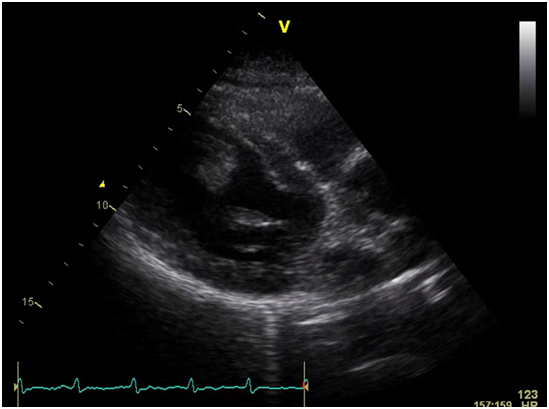

The patient also underwent numerous radiological studies, an abdominal x-ray showed dilated bowel loops. An emergent CT scan of the abdomen that confirmed a small intestinal ischemia with a superior mesenteric thrombus (Figure 1). Due to this, an echocardiogram was performed which showed a severe global hypokinesia of the antero-lateral left ventricle with a mobile thrombus attached to the akinetic portion of the apex with an ejection fraction of 25 % (Figure 2).

Figure 2 Severe global hypokinesia with akinesis of the anterior, antero-lateral wall and apical segments with a massive mobile thrombus in the left ventricle attached to the antero-septal and antero-lateral wall.